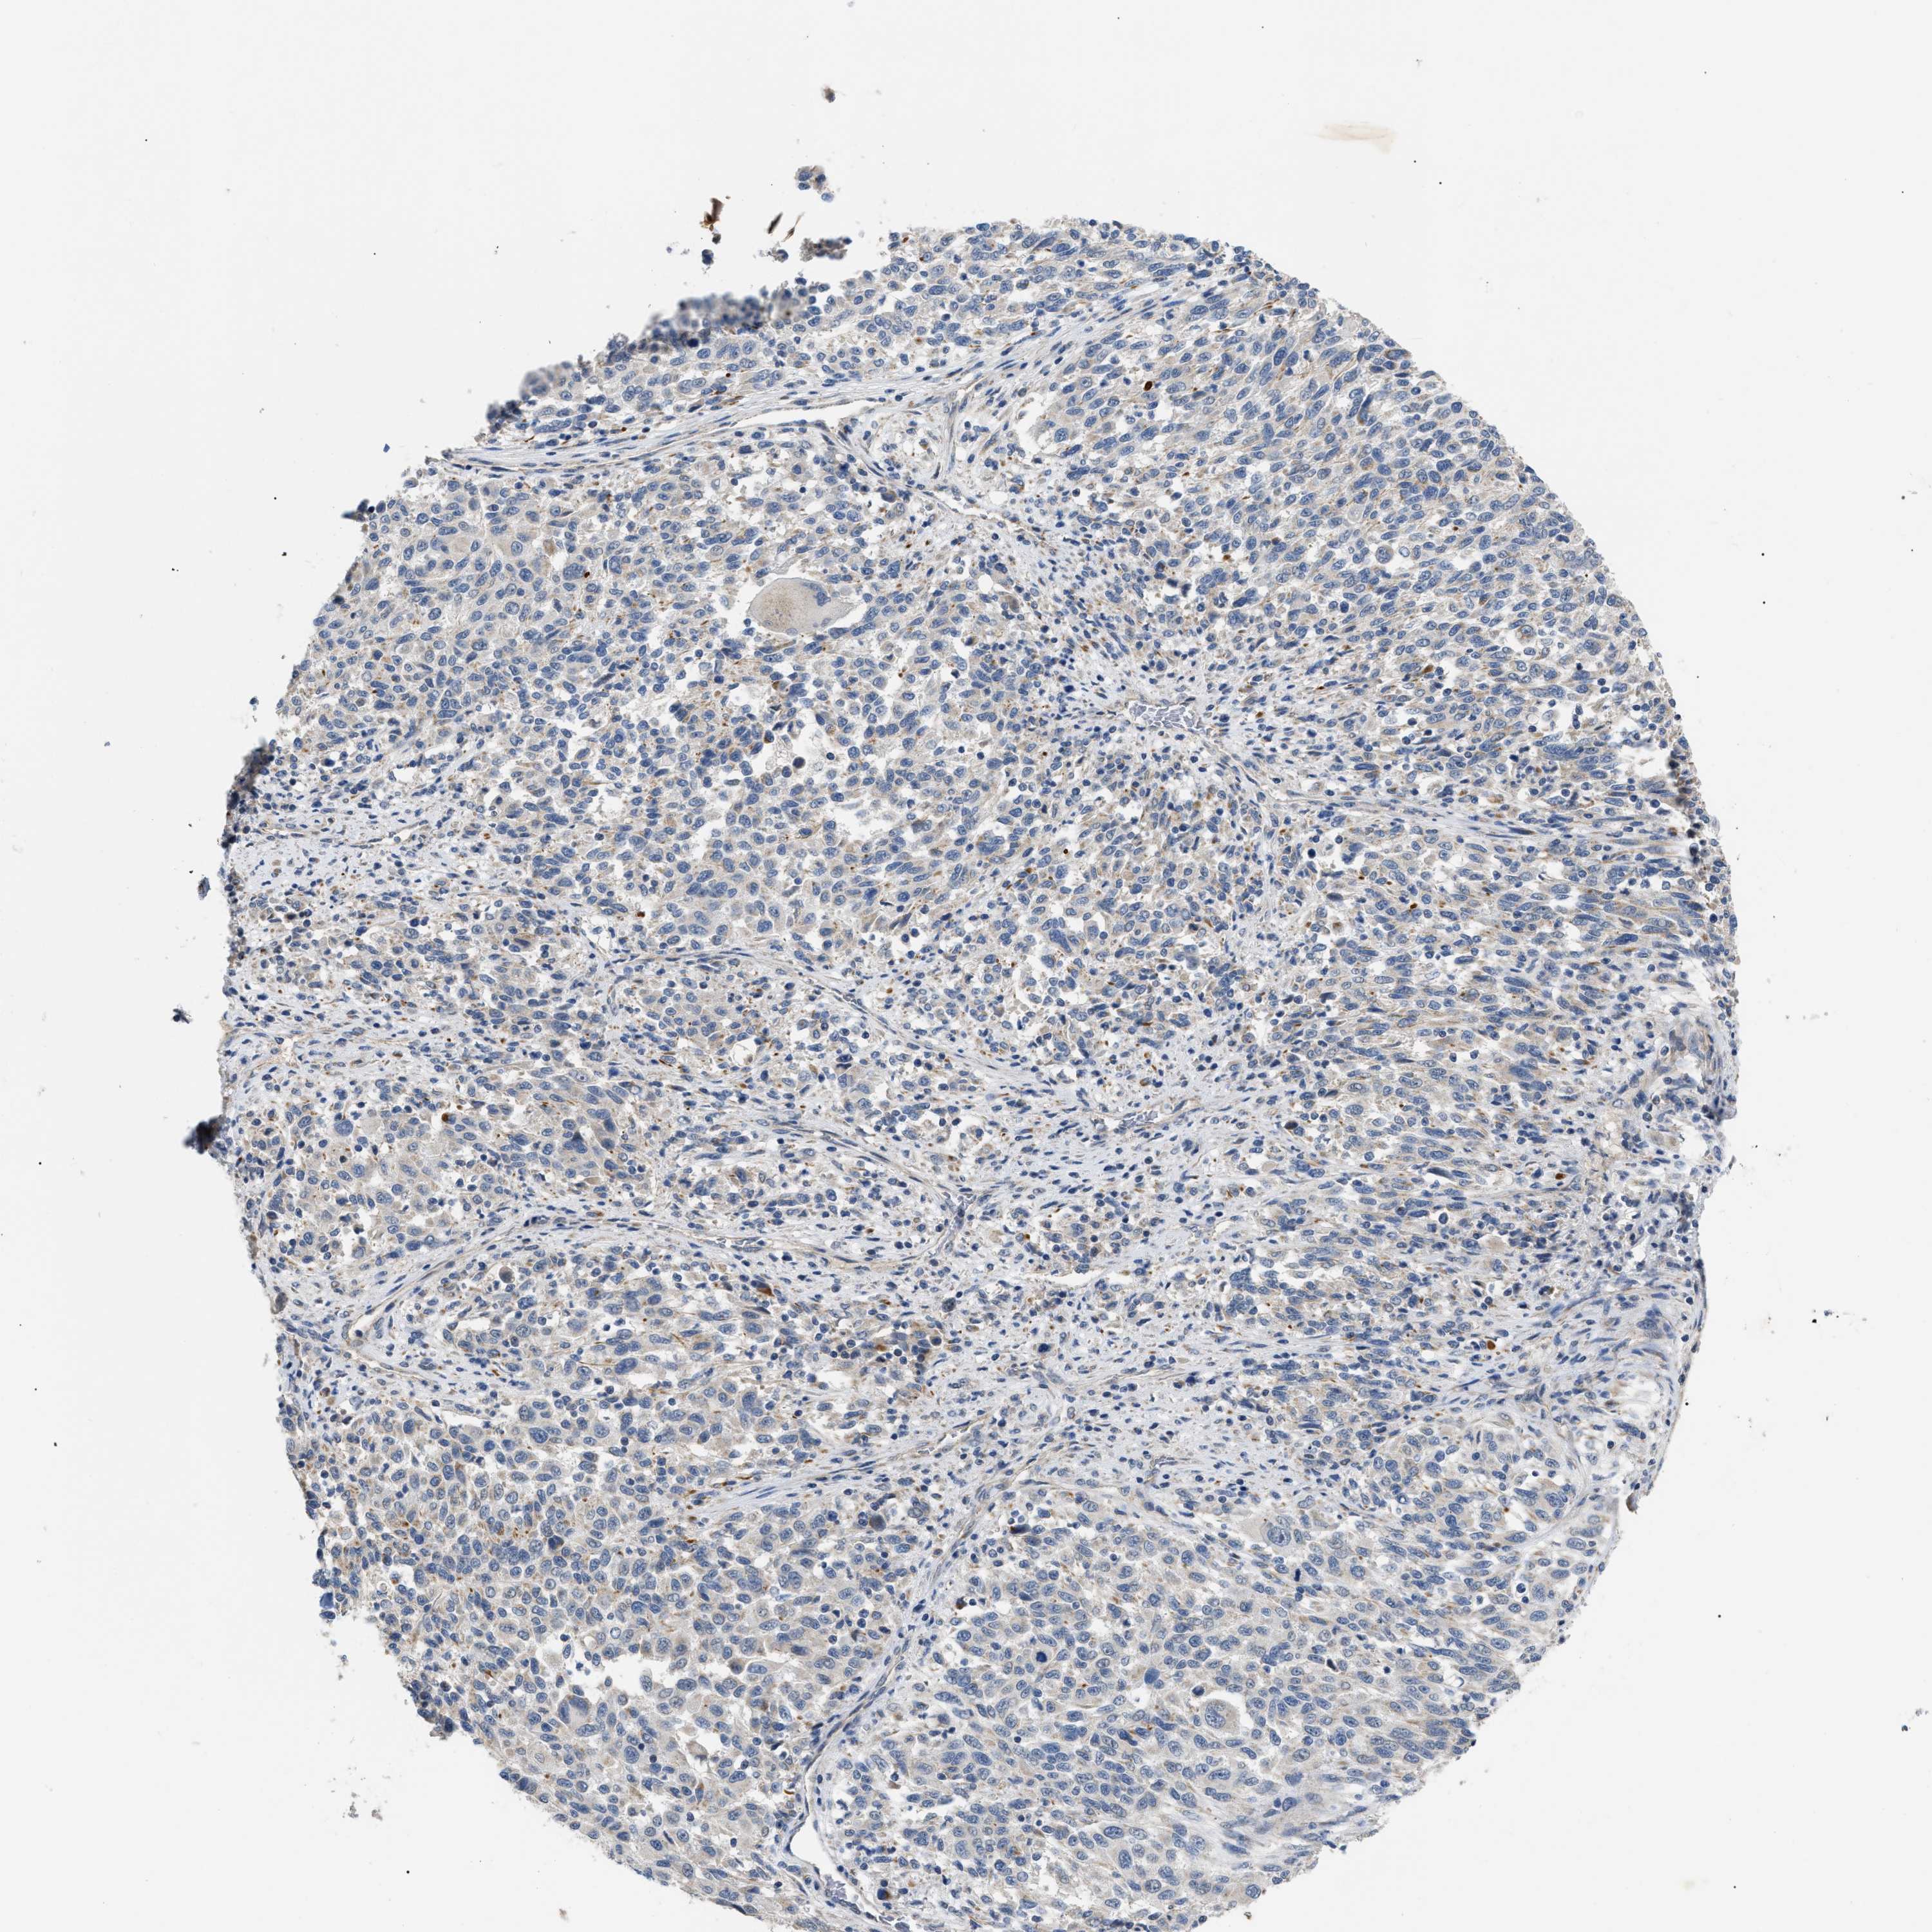

MELANOMA - Protein expressioni

A mouse-over function shows sample information and annotation data. Click on an image to view it in a full screen mode. Samples can be filtered based on level of antibody staining by selecting one or several of the following categories: high, medium, low and not detected. The assay and annotation is described here.

Note that samples used for immunohistochemistry by the Human Protein Atlas do not correspond to samples in the TCGA dataset.

Antibody stainingi

Antibody staining in the annotated cell types in the current human tissue is reported as not detected, low, medium, or high, based on conventional immunohistochemistry profiling in selected tissues. This score is based on the combination of the staining intensity and fraction of stained cells.

Each image is clickable and will lead to virtual microscopy that enables deeper exploration of all samples and also displays staining intensity scores, fraction scores and subcellular localization as well as patient and tissue information for each sample.

Antibody HPA018670

Antibody HPA019570

Staining

High

Medium

Low

Not detected

Intensity

Strong

Moderate

Weak

Negative

Quantity

>75%

75%-25%

<25%

None

Location

Nuclear

Cytoplasmic/membranous

Cytoplasmic/membranous,nuclear

Malignant melanoma, NOS

Malignant melanoma, Metastatic site